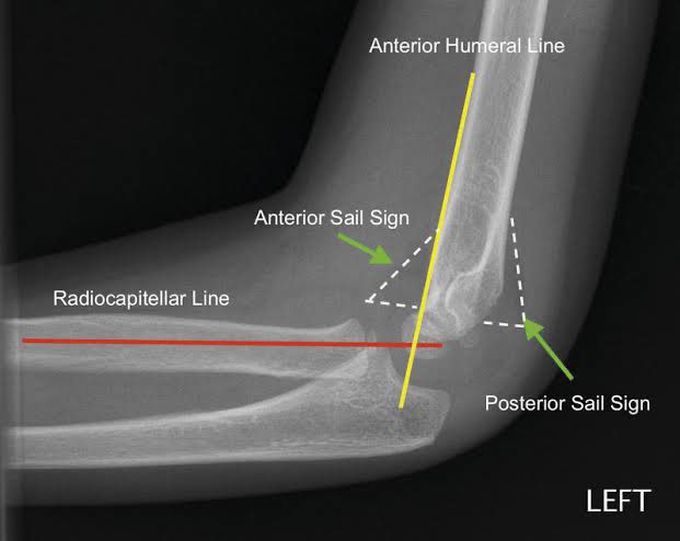

Sail sign (Elbow radiograph): Also called anterior fat pad sign is the lifting up of the anterior fat pad that forms the silhouette resembling the sail of the boat. This sign usually indicated the fracture of radial head in adults and supracondylar fracture in children. Picture credit: https://mforum.com.au/paediatric-elbow-injuries/?amp